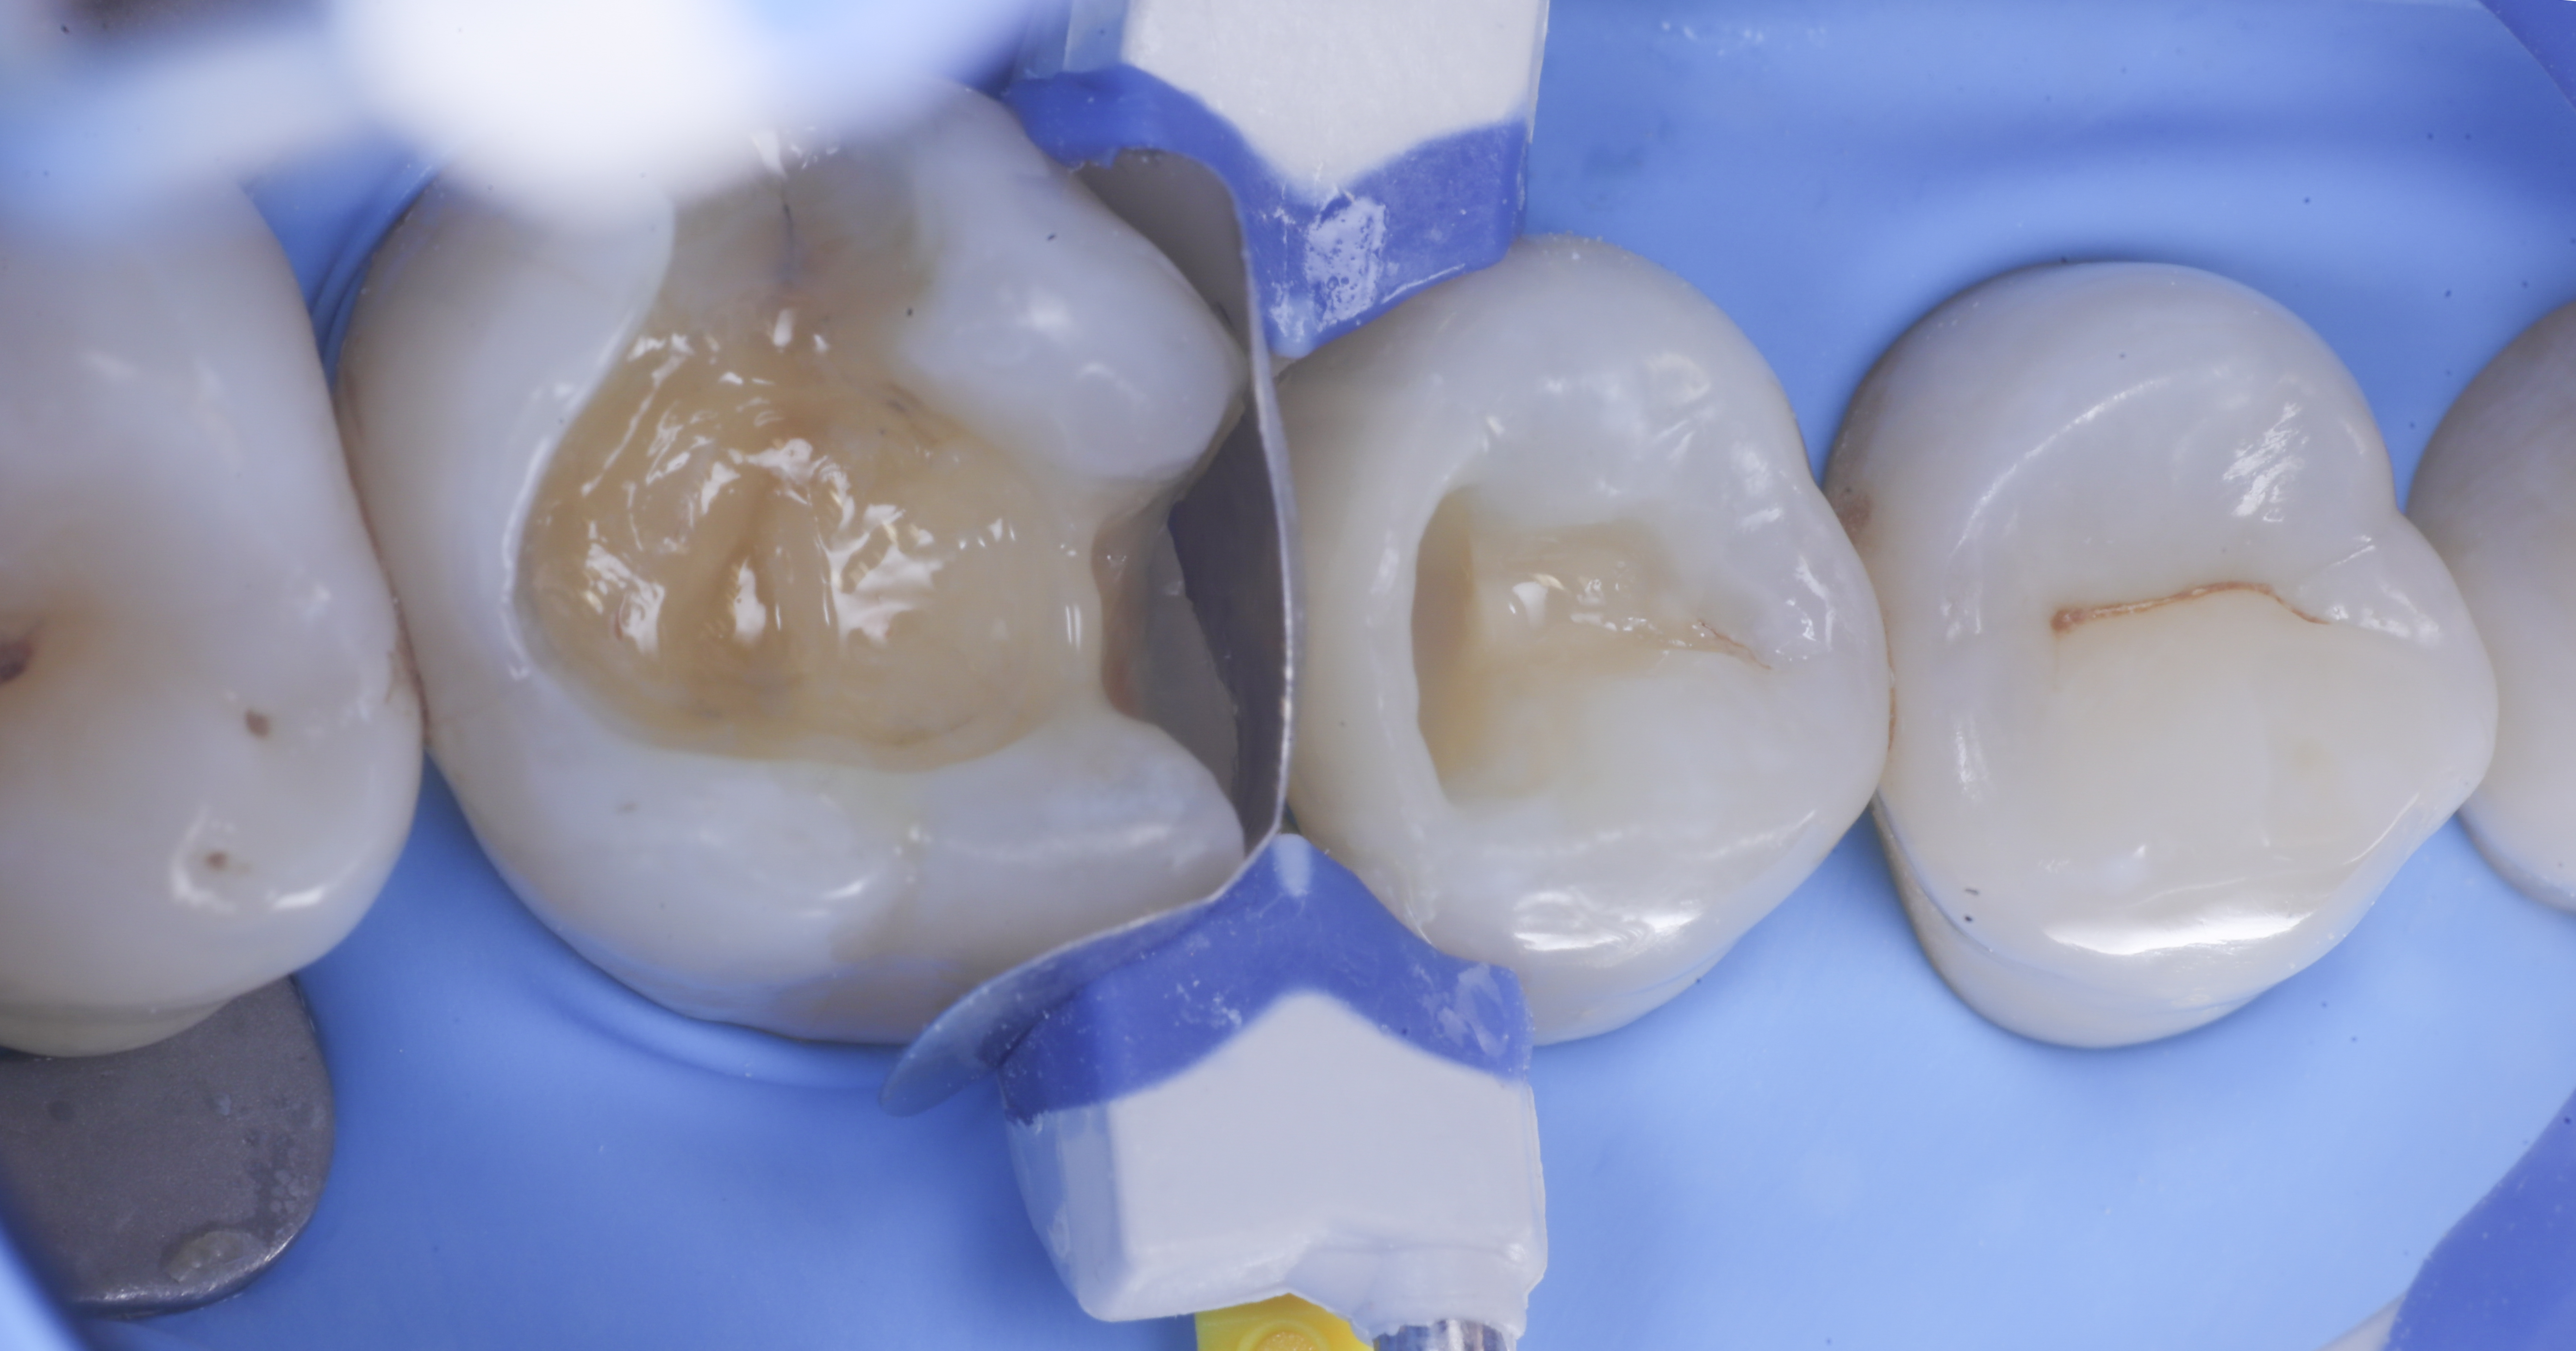

foto 1 Fotografia iniziale

foto 2 Isolamento e aspetto delle cavità ultimate

Una volta eliminato completamente il composito, si procede con la detersione della dentina con frese multilama ed alla rifinitura dei margini di smalto che dovranno essere robusti e puliti.

Dopo il posizionamento del cuneo, anello e delle due matrici sezionai, selezionate per altezza e raggio di curvatura, si procede con l’applicazione dell’adesivo universale, previa pre-mordenzatura dello smalto.